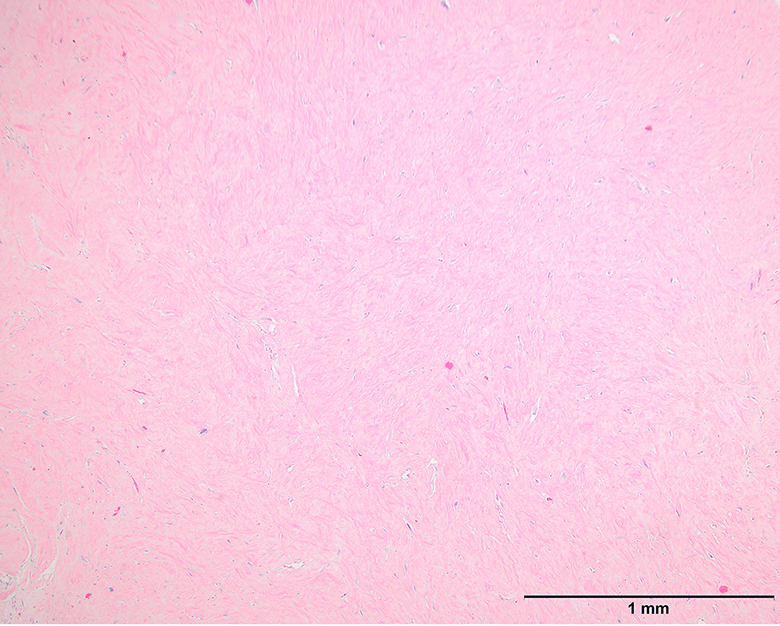

Microscopic (histologic) images

Contributed by Michael Clay, M.D., Melanie Bourgeau, M.D. and AFIP

Morphologic variability:

Microscopic (histologic) description

- Depends on subtype, generally composed of mature fat with variably sized adipocytes and bands of fibrotic stroma containing spindle cells with enlarged, hyperchromatic nuclei

- Can be markedly atypical

- Cellularity is low and mitotic figures are uncommon

- Atypical cells are more commonly found in fibrous septa and in a perivascular distribution

- Lipoma-like subtype

- Most common subtype

- Scattered atypical cells may be diffuse or exceedingly rare

- Frequently contains lipoblasts

- Grossly, can be indistinguishable from lipoma

- Sclerosing subtype

- Second most common subtype

- Predilection for retroperitoneal or paratesticular location

- Collagenous fibrous tissue with scattered adipocytes and atypical multinucleated stromal cells

- Scant lipogenic component may be missed in small samples